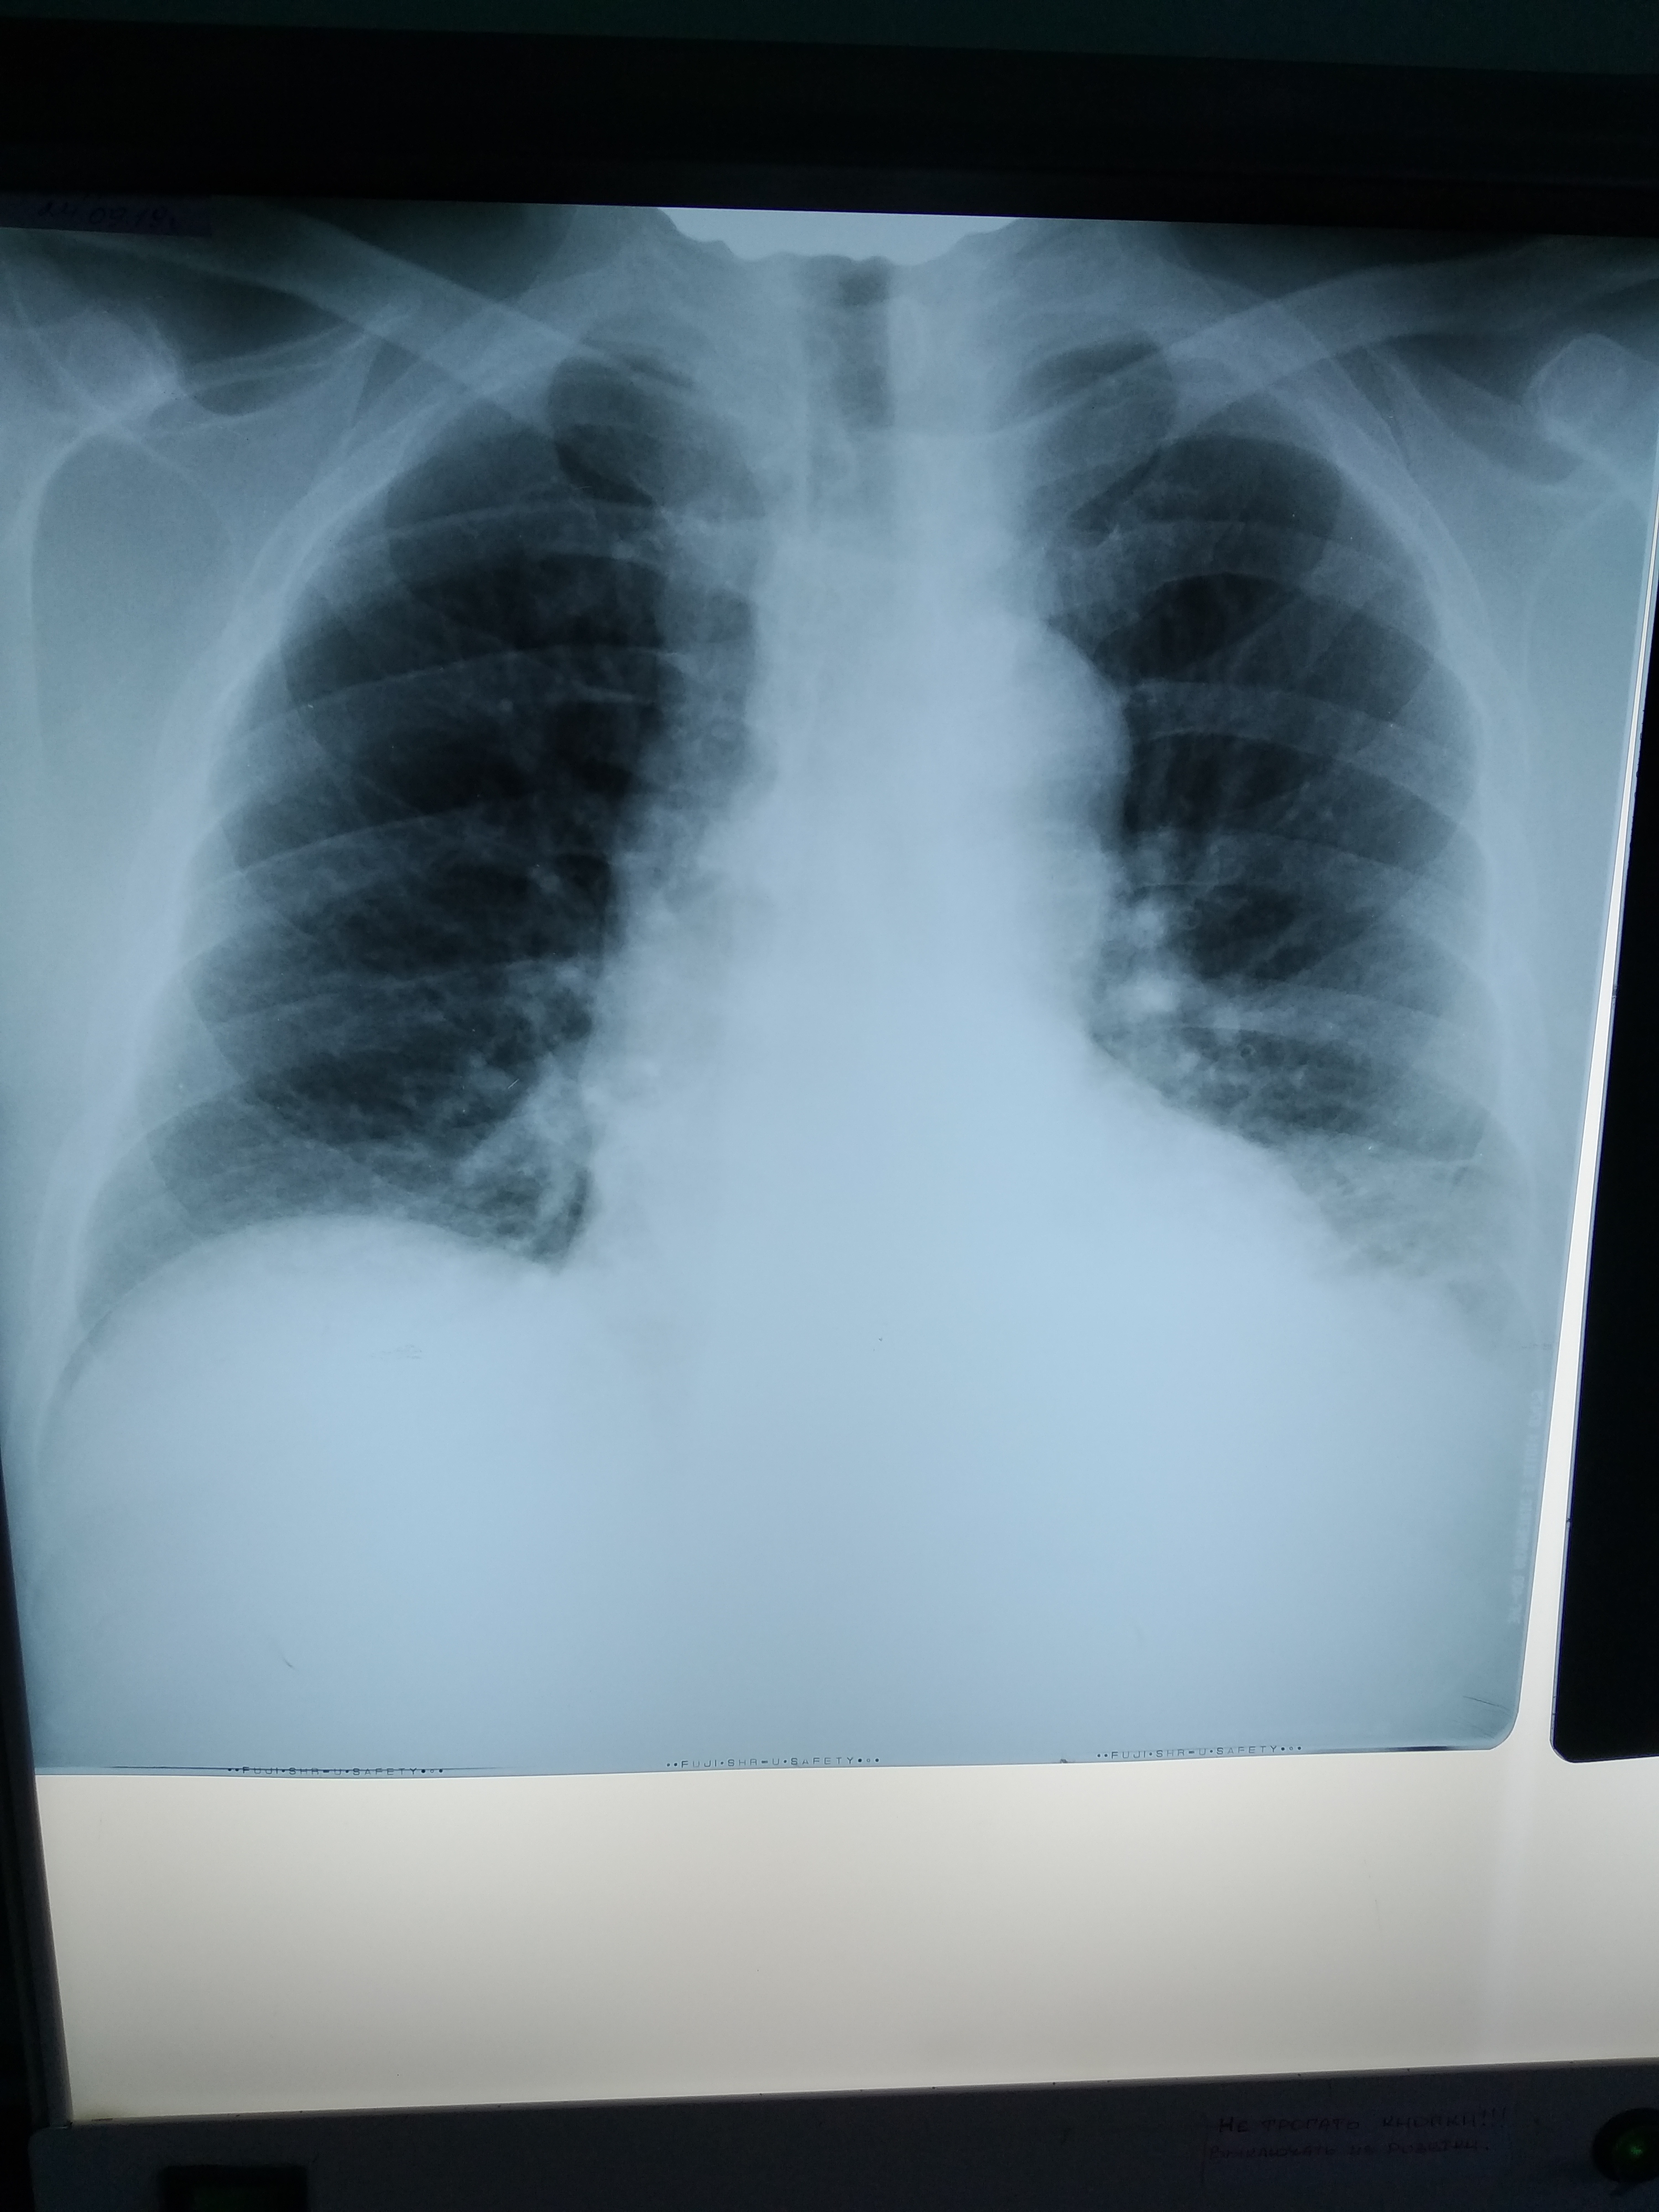

Похоже на опухоль с распадом и нагноением, ателектаз, гидроторакс/плеврит.

Рентгенограмму покажете?

Re: в плевральной полости

Завтра его повезут на КТ. Диск жена обещала купить, поэтому и КТ картинка, возможно, будет.